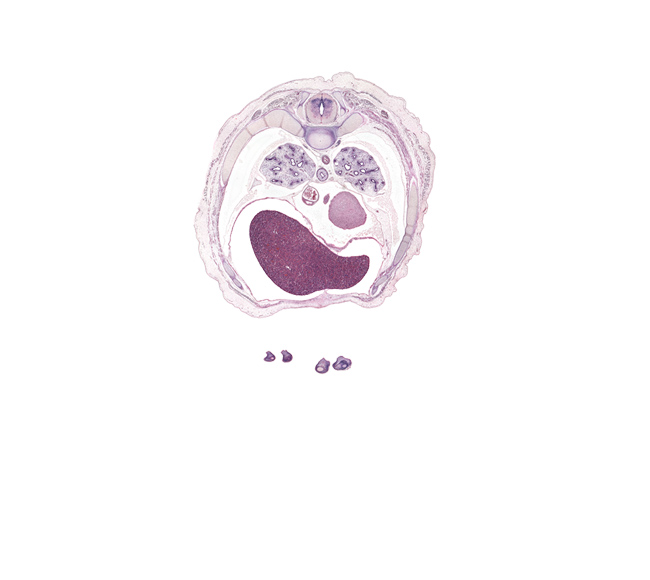

Boyd Embryo #H983 | Location: 121-1-1

Keywords: T-6 / T-7 interganglion region, T-6 / T-7 intervertebral disc, caudal edge of coronary sinus, caudal edge of upper lobe of left lung, central canal, costal margin, distal phalynx of left digit 5 (little finger), esophageal nerve plexus, head of rib 7, latissimus dorsi muscle, left lobe of liver, left ventricle, middle lobe of right lung, neural arch, oblique fissure, pericardial cavity, peritoneal cavity, rib 7, rib 8, rib 9, right lobe of liver, sympathetic trunk, trapezius muscle

Source: The Virtual Human Embryo.